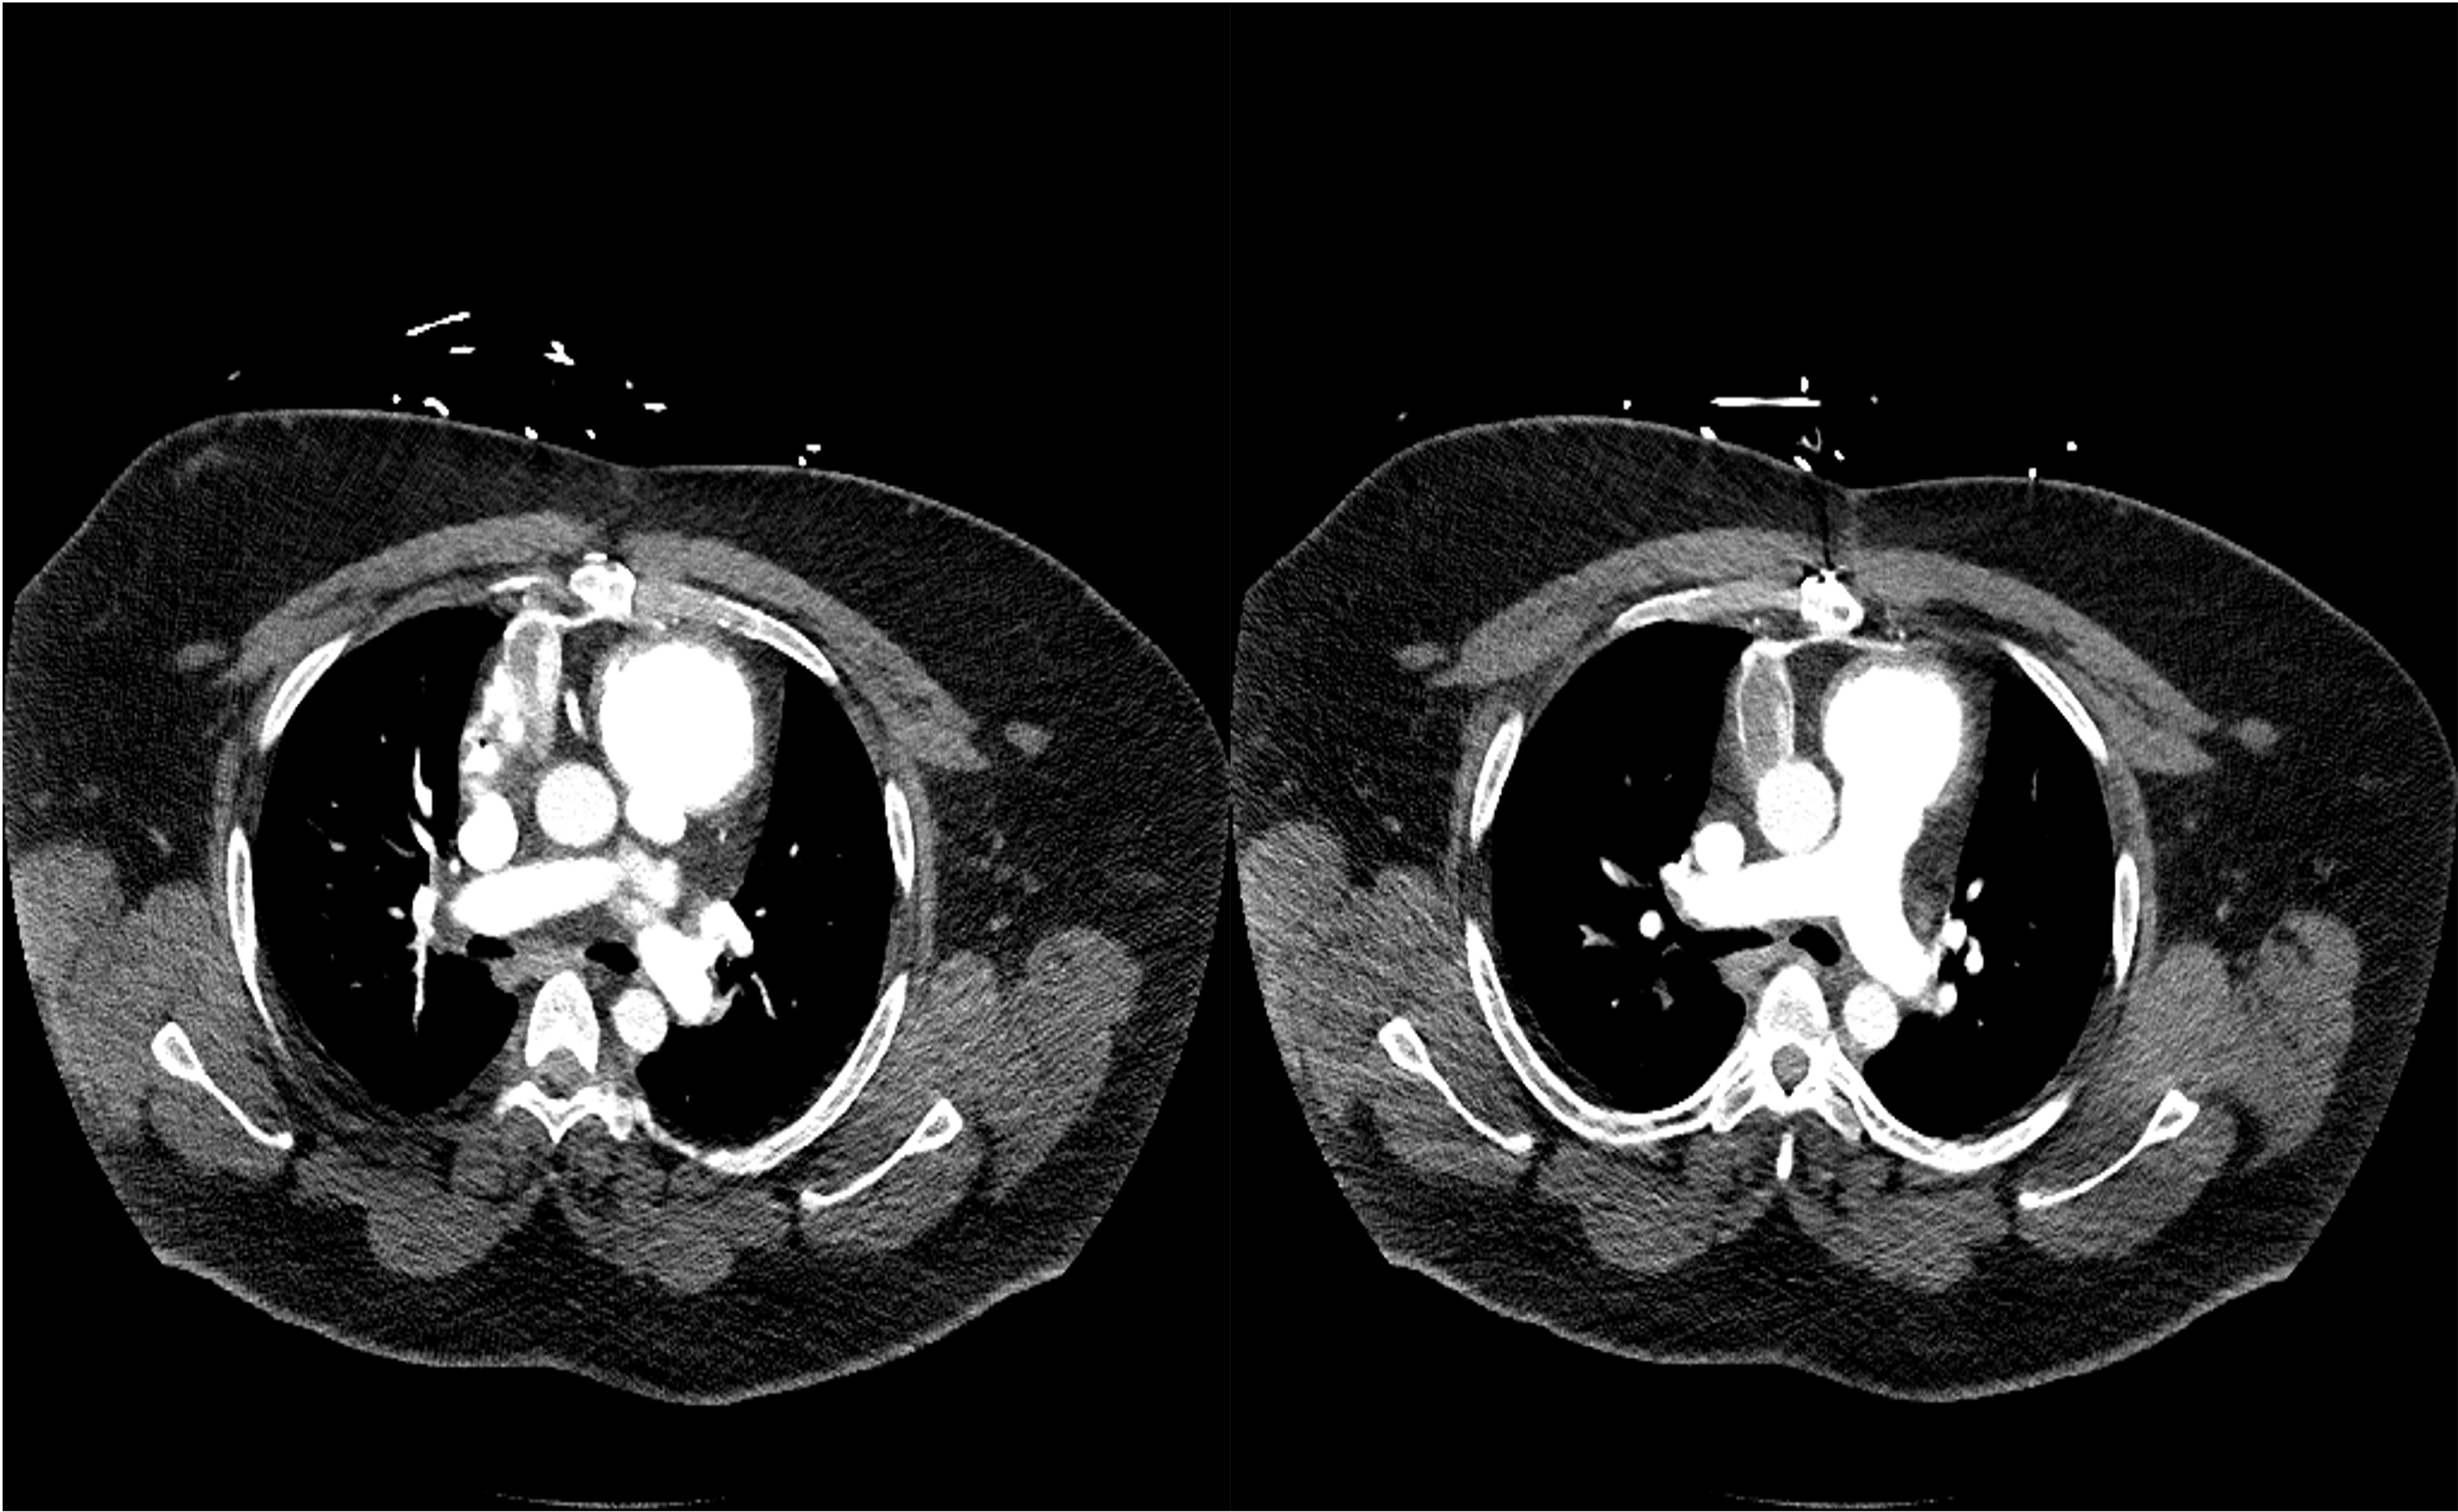

All That Blocks is Not Clot: A Case of Left Ventricular Assist Device Obstruction from Extrinsic Compression

A 36-year-old male with a history of non-ischemic cardiomyopathy status post HeartMate 3 left ventricular assist device (LVAD) presented with a 2-day history of dizziness, lightheadedness, chest pain, and an increase in low flow alarm frequency from his LVAD. On admission, his temperature was 37.2, return to flow was 86, oxygen saturation was 100% on room air, heart rate was 99, and respiratory rate was 23. His lungs were clear to auscultation, and his abdomen was distended, tense, and non-tender. His extremities were warm, with moderate edema in his legs bilaterally. He had mild increased work of breathing without accessory muscle uses. Laboratory evaluation revealed a prothrombin time of 2.6 seconds, a B-type natriuretic peptide level of 176 pg/mL, and a hemoglobin of 13.7 g/dL. Imaging revealed a chest CT demonstrating a complete obstruction of the distal outflow cannula near its attachment to the aorta. Patient hemodynamics worsened after admission, necessitating transfer to the cardiac intensive care unit. After an unsuccessful attempt at warfarin reversal and tissue plasminogen activator administration, the patient was eventually taken for surgical intervention with cardiothoracic surgery. During the procedure, there were no signs of outflow graft thrombus; instead, a sizeable peri-graft fluid collection was observed and drained, which relieved the outflow graft obstruction. The patient’s post-operative course was uneventful, and he was eventually discharged home with a resolution of his symptoms.